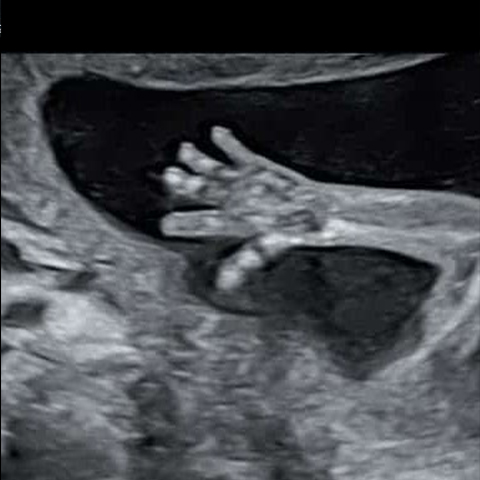

אין להשכח שבסוף הכל רק דברים קטנים. תמיד יש אפשרות לקפוץ לבדיקת יתר או דימות, רק כדי לוודא שהכל נקי ובסדר